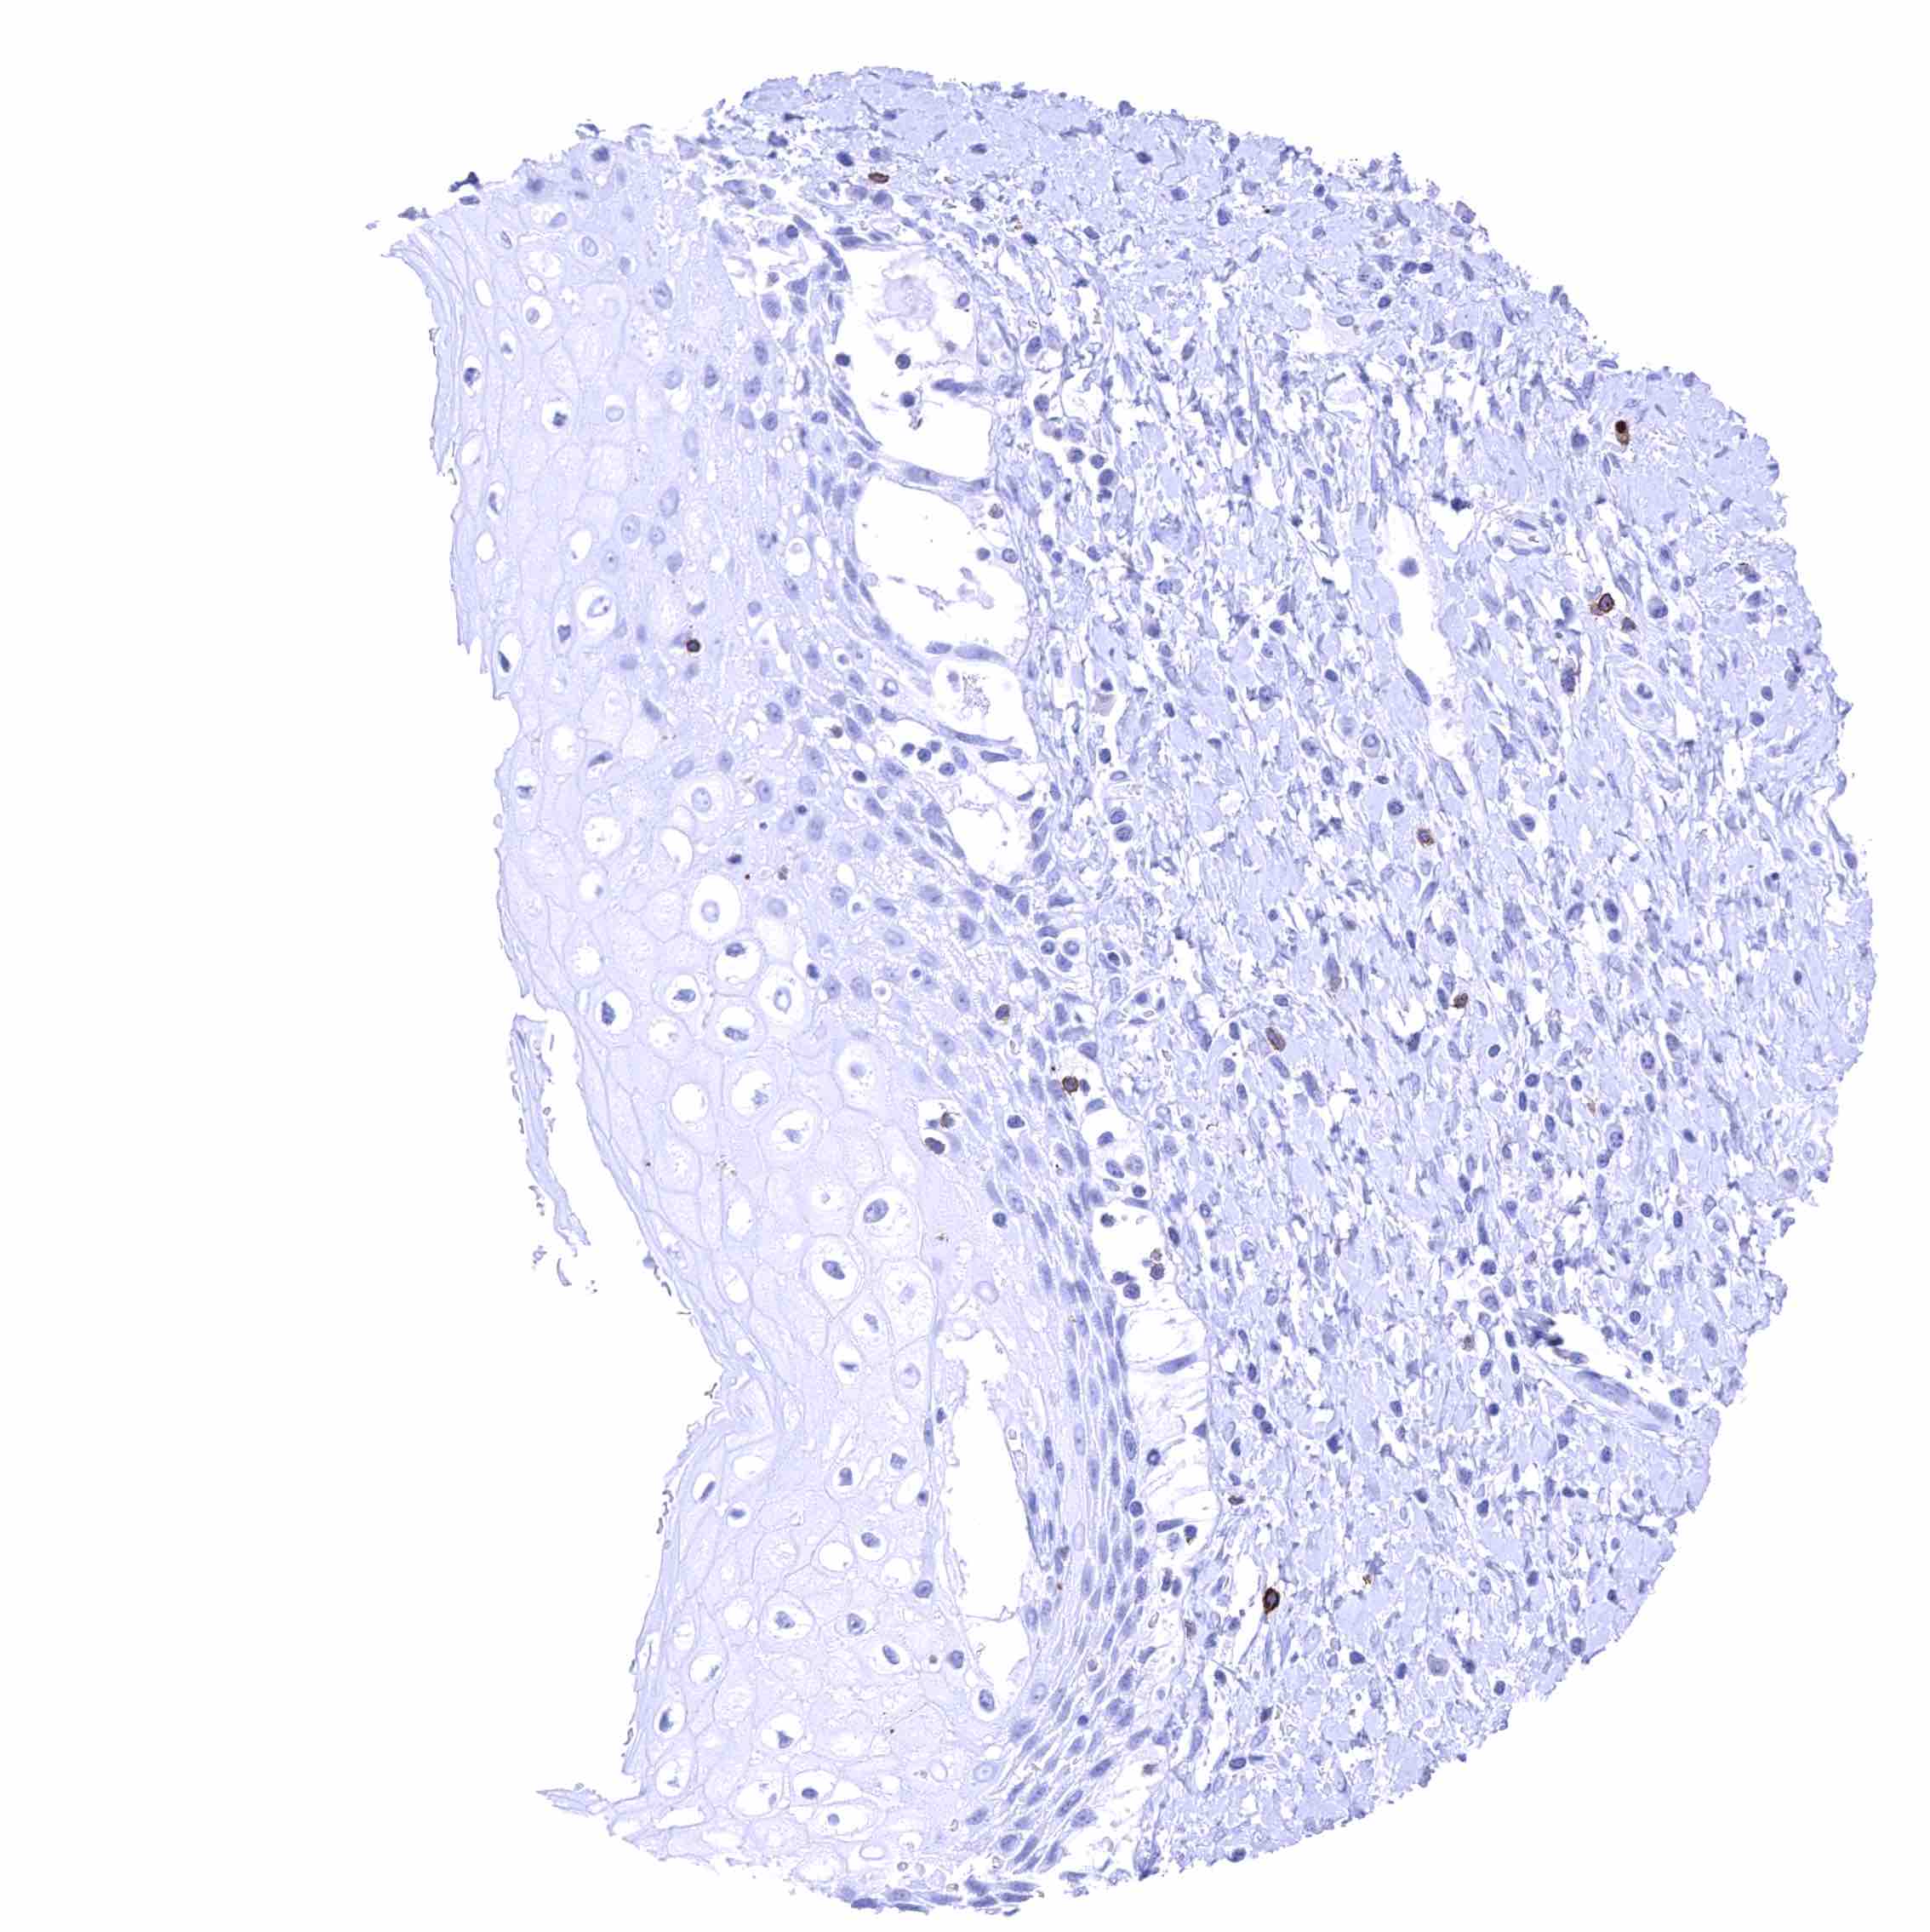

Skin – Membranous CD70 staining of few intraepithelial cells (probably lymphocytes).

Skin, hairfollicel and sebaceous glands